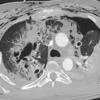

laceration

Date: 07/26/2006

Views: 4315